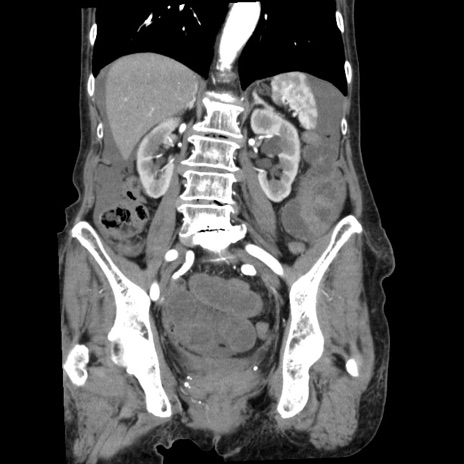

症例1(冠状断像)

【症例】80歳代女性

【主訴】腹痛

【現病歴】8時間前から腹痛あり来院。

【既往歴】糖尿病、脂質異常症、子宮体癌にて子宮全摘術

【身体所見】意識清明・会話良好だが腹痛で苦悶様、全腹部にわたって反跳痛と圧痛あり

【データ】WBC 13600、CRP 0.14、LDH 224、CK 90